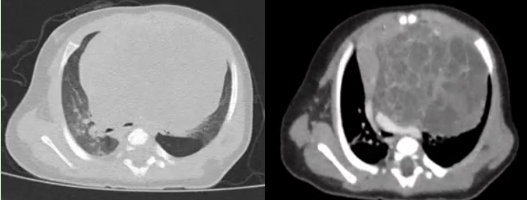

近日,一名仅2月龄、体重只有5.2kg的男婴,因胸闷、呼吸困难来华西医院小儿外科徐畅主任医师处就诊。经CT检查发现,其纵隔内有一个巨大肿块,最大直径 7.4×6.0cm,像胸腔里长一个巨大的“石榴”,严重压迫心脏、左主支气管及肺动脉,不尽快摘除,随时可能引发呼吸循环衰竭,危及生命。

患儿胸部CT影像